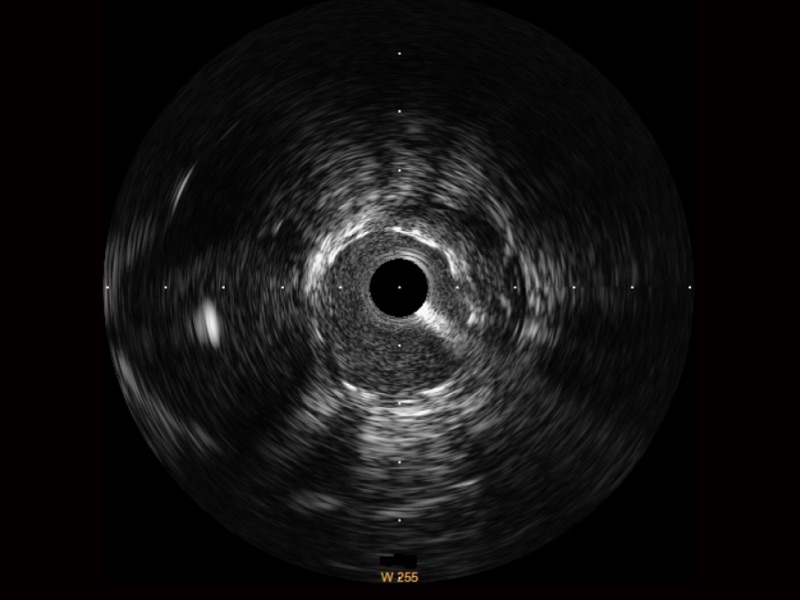

云顶集团官网宽频IVUS图像

传统IVUS图像

对比传统IVUS导管成像,云顶集团官网宽频IVUS图像的近场支架梁显影更细腻,远场中膜外血管仍清晰可辨,兼顾远中近,兼顾分辨力与穿透深度